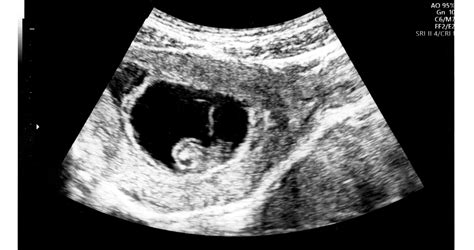

A terhesség alatt számos olyan testi változás és jelenség figyelhető meg, amelyek sokszor ismeretlenek vagy aggodalomra adnak okot a kismamák számára. A reggeli rosszullétek és a duzzadt lábak mellett ott vannak a terhesség furcsa mellékhatásai is, mint a horkolás vagy a hirtelen arcszőrnövekedés, amelyekről már kevesebbet beszélünk. Bár úgy tűnhet, hogy néhány nagyon rendellenes dolog folyik a testünkben, többségük teljesen normális. Az egyik ilyen jelenség a magzati csuklás, amely sok kismamában felvet kérdéseket.

A csuklás egy élettani jelenség, a rekeszizom szaggatott, önkéntelen összehúzódása, mely már magzati korban is jelentkezhet. A magzati csuklás a rekeszizom ritmikus összehúzódása, amely a baba légzőrendszerének fejlődésével függ össze. A rekeszizom egy izom, amely a mellkas és a hasüreg között helyezkedik el, és a légzésben játszik kulcsszerepet. A magzati rekeszizom kifejlődése már a 10. héten megtörténik, és ekkor indul meg a magzat légzőmozgása és emésztési tevékenysége is, mely során a magzat már nyelni tudja a magzatvizet.

A szakemberek szerint a magzati csuklás szoros összefüggésben áll az idegrendszer érésével is. A reflexek kialakulása és finomodása során az agy és az izmok közötti kommunikáció néha „túlszalad”, és ez váltja ki az ismétlődő rángásokat. A csuklás során érkező ingerek segítik az agyat abban, hogy feltérképezze a testet és az izmokat. A magzati csuklás valójában egy reflexszerű izomösszehúzódás, amely a rekeszizom rángatózásából ered. Bár mi, felnőttek, gyakran kellemetlennek éljük meg a csuklást, a magzat számára ez egy természetes folyamat, amely már az első trimeszter végén, a második trimeszter elején elkezdődhet.

A legtöbb kismama a második vagy harmadik trimeszterben, általában a 24. hét után kezdi érezni a baba csuklását. A 24. és 32. hét között a magzati csuklás még gyakoribbá válhat. A harmadik trimeszterben a csuklás intenzitása fokozódhat. Ilyenkor már nemcsak érezni, hanem látni is lehet: a hasfal ritmikus ugrálása néha egészen mulatságos látványt nyújt. Nem ritka, hogy a baba naponta háromszor-négyszer is nekiáll csuklani, ami alkalmanként akár tíz-húsz percig is eltarthat. A szüléshez közeledve, a 36. hét után egyes babáknál ritkulhat a csuklás, míg másoknál az utolsó pillanatig kitart.